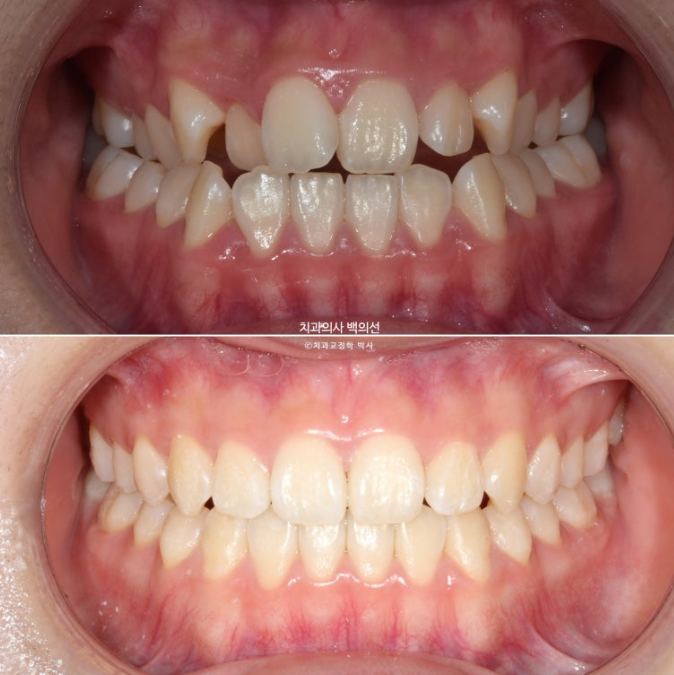

치료 전 후 보겠습니다.

23.10~25.04

24.10

24년 10월까지 8개월간 첫번째 세트 장치를 모두 낀 후 모습입니다.

24년 11월부터 25년 4월까지 5달간 추가장치를 낀 후 치료를 종료했습니다.

중심선은 정확하게 맞으며 앞니 교합은 좋습니다.

추가장치를 끼는 동안은 3급 고무줄을 내내 걸면서 앞니 교합 안정을 도모했습니다.

총 치료기간은 1년 6개월입니다.

그 중 4개월은 악궁확장기간, 인비절라인 장치를 낀 기간은 1년 2개월이며 나머지는 인비절라인 장치 제작기간이었습니다.